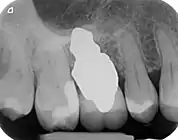

RAIs are custom made to perfectly fit the tooth socket of a specific patient immediately after tooth extraction. Therefore every implant is unique. As an optimized root-form it is much more than a simple 1:1 replica of a tooth. Since it exactly fills the gap left after the tooth is extracted, surgery is rarely needed. The implant can be produced from a copy of the extracted tooth, an impression of the tooth socket, or from a CT scan or CBCT scan.[3] The advantage of a CBCT scan is that the implant can be produced before extraction. With the former methods, it takes one or two days to fabricate an implant.

- Natural form: a custom milled anatomic implant replicates the natural form of a tooth, so it simply fits into the tooth socket. Like the original tooth, a root analogue implant can have single- and multi-rooted forms.

- Esthetic: a ceramic RAI closely resembles a natural tooth in color. Thus there is no discoloration through the gums, as is commonly seen with titanium implants.

A new attempt was made by Pirker et al 2004 in a human trial with root analogue zirconia implants, but this time by applying differentiated osseoingration on the surface. In 2011 he reported 90% success rate with this method in a 2.5 year human trial.[11]

- 1 2 3 Pirker, W; Wiedemann, D; Lidauer, A; Kocher, A (2011). "Immediate, single stage, truly anatomic zirconia implant in lower molar replacement: a case report with 2.5 years follow-up". International Journal of Oral and Maxillofacial Surgery. 40 (2): 212–6. doi:10.1016/j.ijom.2010.08.003. PMID 20833511.